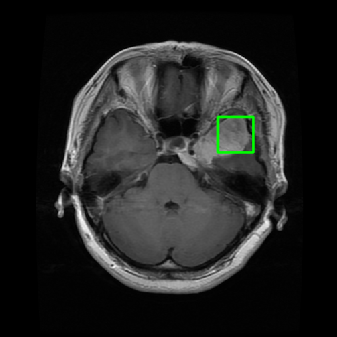

4.2 Comparison with brain tumor MR images segmentation

Brain tumor MRI images represent a critical challenge within the field of medical image analysis, making them a focal point of our research. Various level set models for image segmentation have been applied to brain tumor MRI images, and it is essential to consider the unique characteristics of these images. To validate the excellent performance of the RefLSM, we conduct segmentation comparison experiments on brain MR images and compute the Dice coefficient and Precision values for all evaluated models.

Fig. 4 displays the visual comparison results for segmenting eight brain tumor MR images between the RefLSM and three representative models: the RESLS [8765635], ALF[MA2019201], and L1 model[LIU2019193]. These images exhibit severe intensity inhomogeneity and noise attributable to inconsistent bias field and imaging equipment. The initial level set function (LSF) initialization was consistent across all models, as shown in Fig. 4 (a), which illustrates the initial placement of the zero level contour. For visual clarity, we included the ground truth in Fig. 4 (f). The segmentation outcomes from the RESLS, ALF, and L1 methods are presented in Fig. 4 (b), (c), and (d), respectively.

It is evident from the first and last columns of Fig. 4 (b) that the ALF model tends to become trapped in local minima under severe intensity inhomogeneity. Furthermore, segmentation results presented in the columns 1-4 of Fig. 4 (b) and (c) reveal that both the ALF and L1 models mistakenly segment small isolated or irrelevant regions due to the effects of irregular intensity patterns. Additionally, when weak boundaries are present, as seen in the 1st and 3rd columns of Fig. 4, the RESLS, ALF, and L1 methods fail to accurately identify object boundaries. Consequently, the zero level contours of these models deviate significantly from the objects throughout the level set evolution, causing drastic misalignment after further iterations.

In stark contrast, our proposed method exhibits greater robustness against images exhibiting severe intensity inhomogeneity and weak boundaries. The proposed prior constraint term effectively corrects for intensity inhomogeneity, while the proposed binary level set adeptly reduces noise during the segmentation process.

Overall, these findings demonstrate that the segmentation outcomes produced by our model are more accurate. Besides visual assessment, we calculate the Dice and Precision values of evaluated models for brain tumor segmentation in table 1. Based on these results, we draw a boxplot with scatterplot overlay, as shown in Fig. 6, which displays the data distribution and facilitates comparison of different models’ performance across various brain tumor MR images. We analyze the maximum, median, and minimum, which correspond to the best, median segmentation results, and worst segmentation results, respectively. It is clear that the RefLSM achieves more accurate segmentation results compared to the other models. Moreover, the smaller range of the RefLSM in the boxplot indicates robustness and stability to different images of the brain tumor.